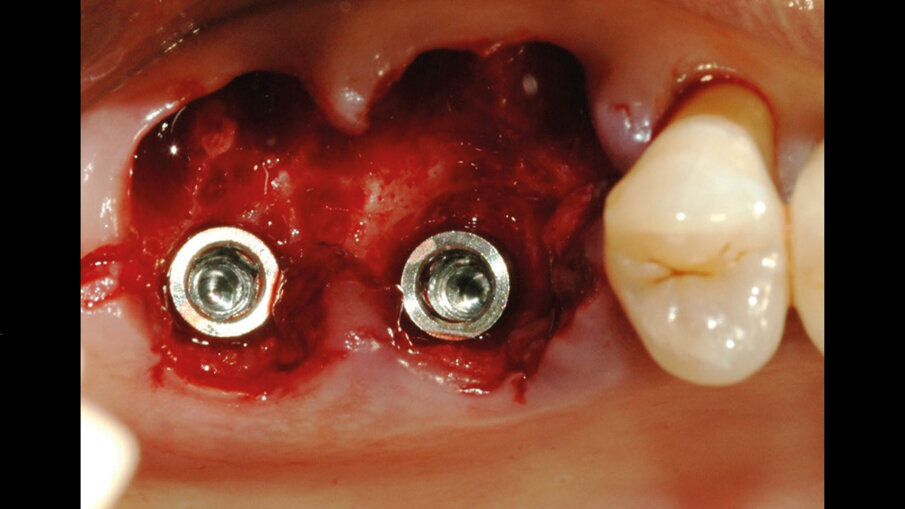

Il giorno prima dell’intervento, la paziente veniva sottoposta a terapia antibiotica con Amoxicillina e Acido Clavulanico compresse da 1 gr ogni 12 ore. Il giorno dell’intervento veniva eseguita la profilassi antibiotica 1 ora prima dell’inizio con 875/125 mg di Amoxicillina+ Acido Clavulanico e veniva praticata l’anestesia locale con Articaina + adrenalina 1:100.000. Quindi si procedeva all’estrazione dei due elementi compromessi (Fig. 2) e si provvedeva alla preparazione del sito implantare all’interno della radice palatina; gli autori considerano questa la sede di elezione ove la zona del setto inter-radicolare non fosse idonea ad accogliere l’impianto. Una volta preparati i tunnel implantari nei siti 26 e 27, venivano inseriti due impianti 4.3 x 10 mm (IDI evolution Tiger) (Fig. 3). La stabilità implantare veniva misurata mediante il rapporto e lo scambio di energia tra la superficie di contatto ossea e l’impianto ottenendo un valore oggettivo (Newton/cm) che rappresenta la stabilità implantare (TMM3 IDI evolution) (Fig. 4).

Fig. 3 - Inserimento dei due impianti 4.3 x 10 mm (IDI evolution Tiger) all’interno dello spazio alveolare.

Per colmare il gap tra impianti e osso si eseguiva un mantenimento alveolare a livello dello spazio lasciato vuoto in seguito all’estrazione delle radici vestibolari mediante l’impiego del cilindro di pasta ossea liofilizzata (Fig. 5). La pasta ossea liofilizzata, una volta idratata con il sangue intra-operatorio del paziente, diventava malleabile e andava a colmare perfettamente i difetti peri-implantari. L’innesto veniva ricoperto con la matrice collagenica tridimensionale che garantiva una protezione di 2-4 settimane oltre a costituire il substrato adatto alla proliferazione dei fibroblasti e favorire la guarigione dei tessuti molli attorno agli impianti (Figg. 6, 7). Venivano applicate le viti di guarigione e i lembi venivano chiusi con delle suture in Monomyd 5-0 per favorire la guarigione per seconda intenzione (Fig. 8). L’RX post-operatoria confermava il corretto posizionamento implantare (Fig. 8). Dopo l’intervento, il paziente seguiva una terapia domiciliare a base di amoxicillina ac. clavulanico 875/125 mg: 1 compressa ogni 12 ore per 7 giorni. In aggiunta, nimesulide per i primi 2 giorni. A livello della sede operata, venivano prescritto un gel a base di Clorexidina da applicare 2 volte al giorno, per 10 giorni. Ad un mese dalla procedura chirurgica, l’aspetto clinico mostrava il buon procedere del processo di guarigione dei tessuti molli. A sei mesi di distanza si osservava una completa maturazione dei tessuti perimplantari (Fig. 9). Venivano quindi prese le impronte e successivamente consegnate le protesi provvisorie a carico degli elementi 26, 27. Tre mesi più tardi, dopo aver raggiunto la completa maturazione dei tessuti duri e molli, previa impronta analogica, venivano realizzate le protesi definitive. L’RX di controllo mostrava l’ottima integrazione degli impianti. La paziente era soddisfatta (Fig. 10).